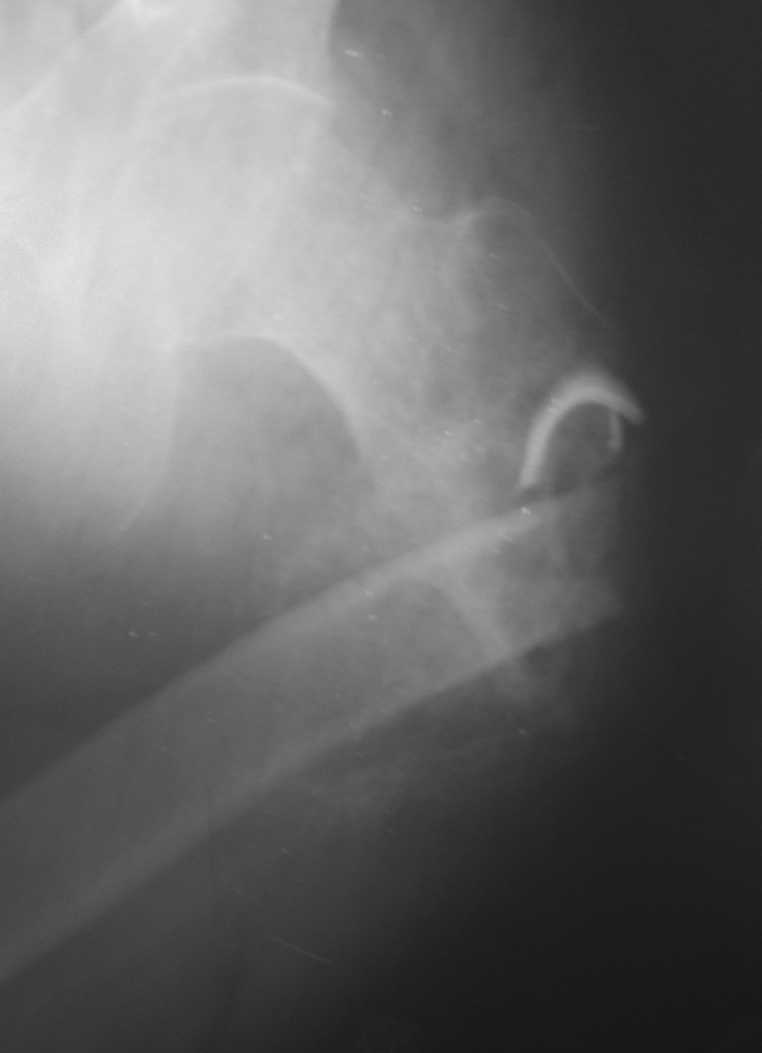

Произведена секвестрэктомия, остеотомия костной мозоли(кстати говоря мозоль оказалась довольно таки приличной) Рана ушита нагрухо. Наложено ДСВ за мышелки бедра. Рана зажила первичным натяжением. Пациенту наложен коксит, готовится на выписку.

07-07-2010 11-57-54 AM.png